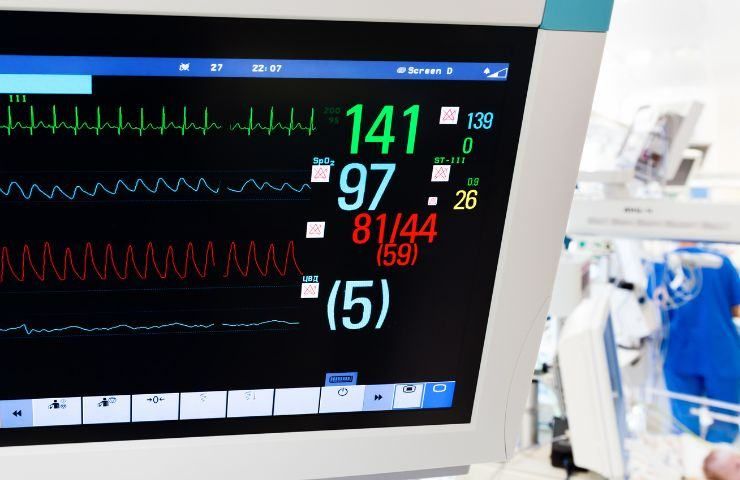

I medici del Gaslini, capitanati dal cardiochirurgo Guido Michielon, sono riusciti a salvare un bambino di appena 6 mesi.

Il bambino soffriva di una cardiopatia molto grave e, secondo i medici inglesi, non poteva essere operato. La possibilità di trovare un cuore compatibile per un trapianto erano veramente scarse e i dottori l’avevano già dichiarato inoperabile.

Tuttavia, i genitori di Adam (nome inventato), provenienti da Londra, non si sono arresi e hanno cercato aiuto presso l’Ospedale Gaslini di Genova, dove il piccolo è stato sottoposto con successo a un intervento chirurgico (lo scorso 17 luglio, n.d.r). Grazie all’abile opera del cardiochirurgo Guido Michielon e del suo team, attualmente, Adam è fuori pericolo.

Come riportato dal Il Secolo XIX, il dottor Michielon ha spiegato che sono stati eseguiti due complessi interventi in una procedura unica, appresa durante la sua formazione negli Stati Uniti dal professor Norwood, noto per aver sviluppato questa tecnica. In passato, Adam aveva già subito un intervento palliativo di emergenza poco dopo la nascita. Secondo le valutazioni dei medici britannici, le cure palliative sembravano essere l’unico percorso per un bambino così giovane, che era in attesa di un trapianto di cuore ma che avrebbe fatto fatica a sopravvivere a un’operazione di tale portata.

Il dottor Michielon ha eseguito un ulteriore intervento altamente complesso il 26 luglio su un giovane di poco più di 20 anni affetto da un difetto congenito della valvola aortica, con dilatazione dell’aorta ascendente e della radice aortica. Questo intervento, denominato “Ross-PEARs”, è stato eseguito per la prima volta in Italia. La procedura consiste nell’autotrapianto della radice polmonare nell’aorta, viene poi applicato un supporto personalizzato in polietilene, creato attraverso una ricostruzione tridimensionale della radice polmonare della persona malata. Questo supporto esterno, costruito su misura, viene creato appositamente per ciascun paziente e rispecchia quindi la morfologia e la struttura della radice polmonare.